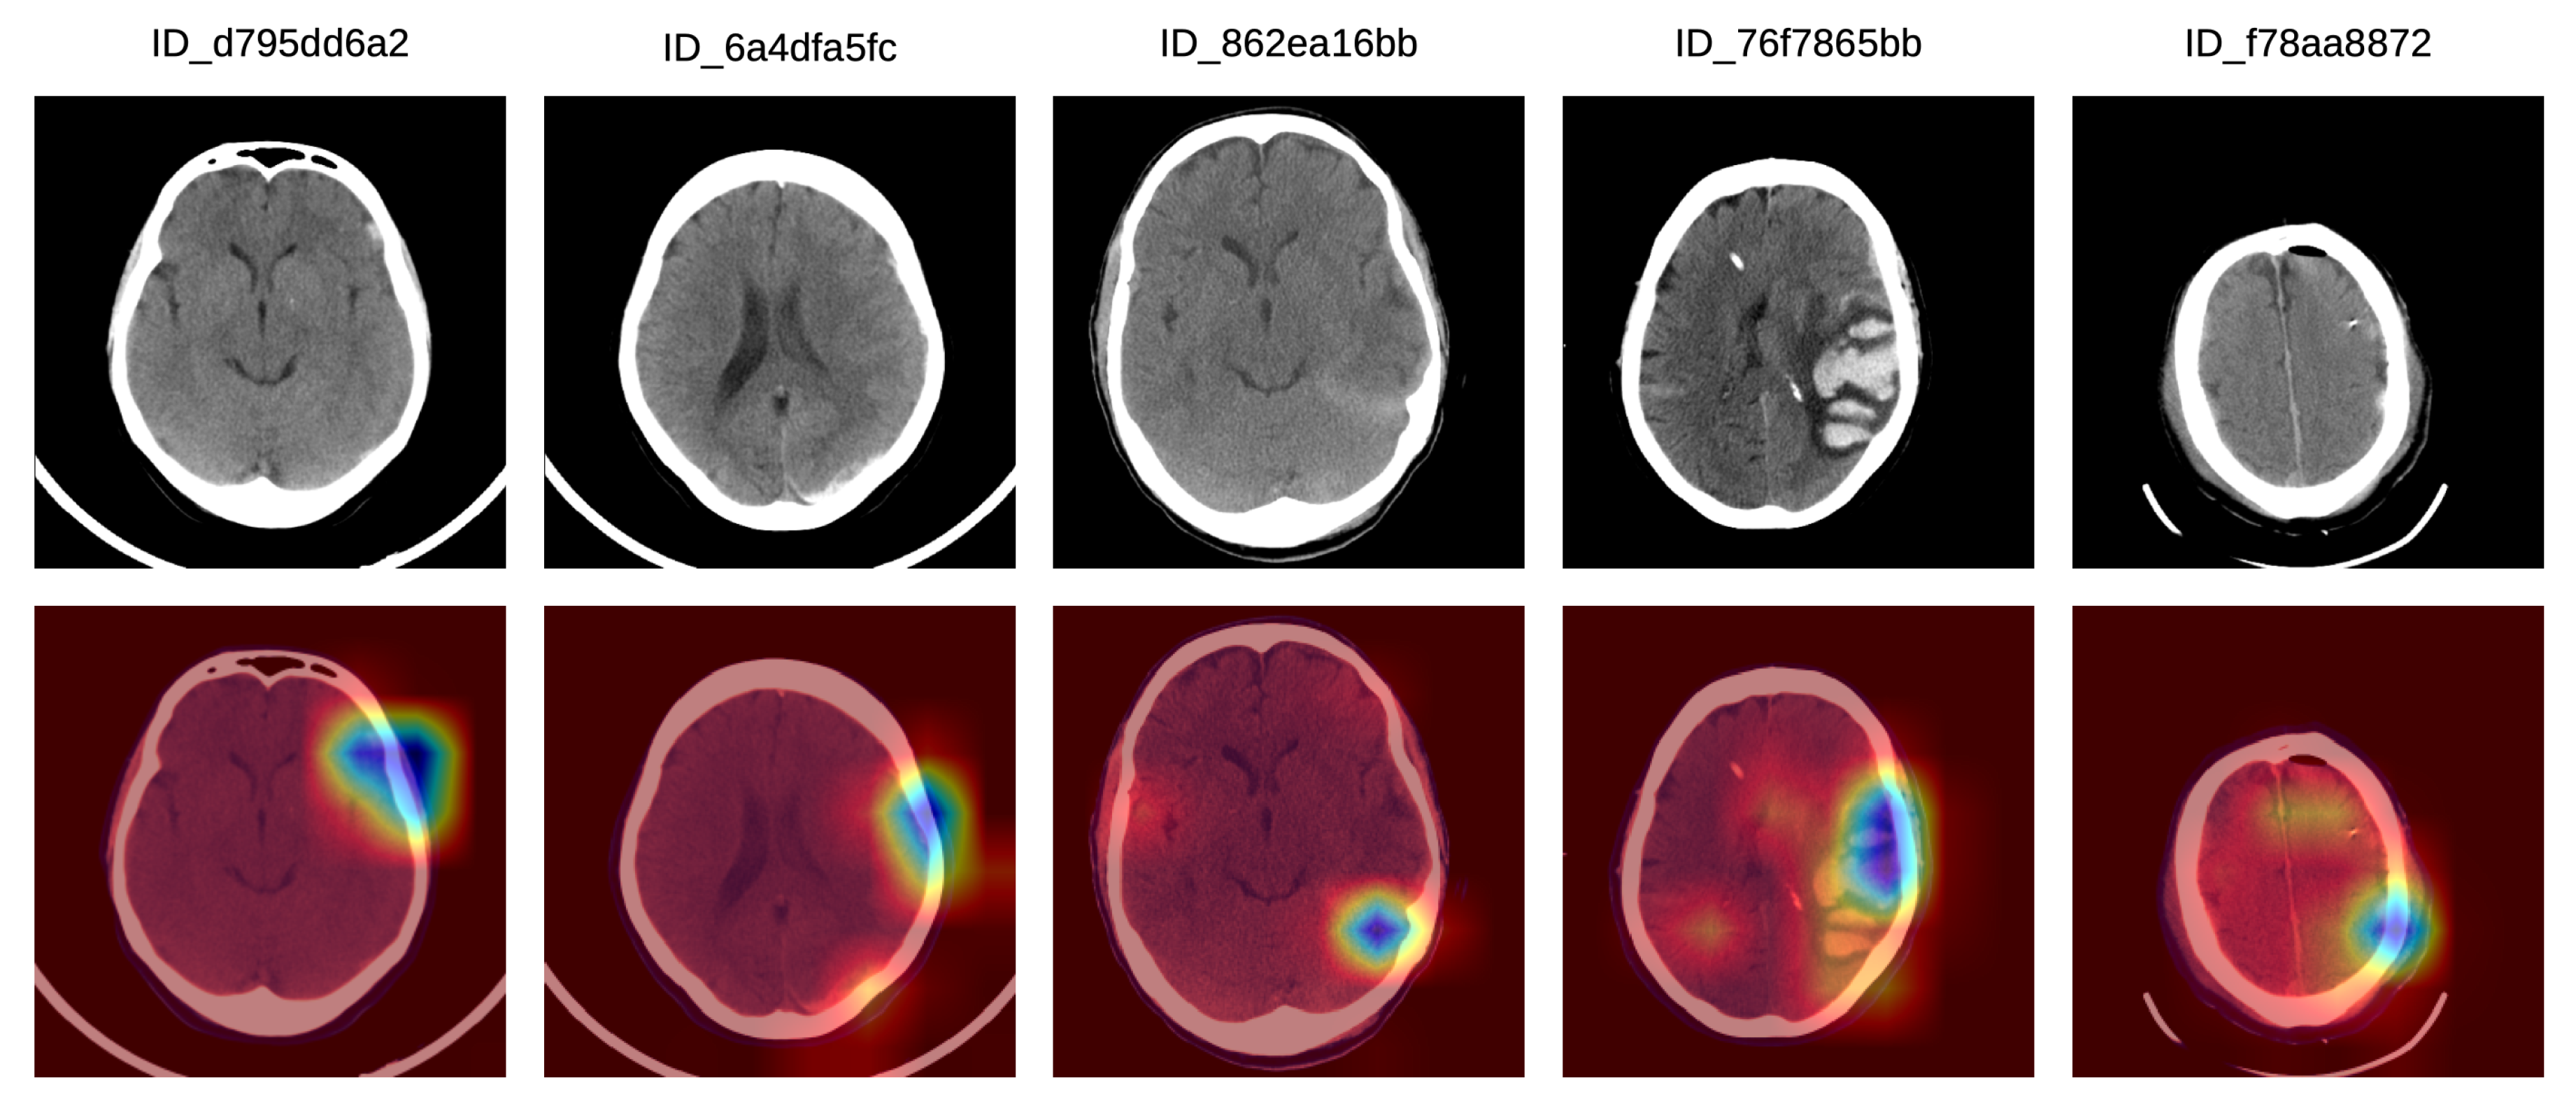

In order to better understand how doctors classified the Grad-CAM visualizations as correct, partially correct or incorrect, we next present a detailed analysis of five particular Grad-CAM examples from each category. In Figure 5, we illustrate a set of Grad-CAM visualizations that were labeled as correct by the doctors. In the first (left-most) sample, the system concentrates on the subdural hemorrhage in the left frontal lobe. In the second sample, the system correctly concentrates its attention on two hemorrhage regions, one in the left frontal lobe and one in the left parietal lobe. In the following two samples, we observe that our system focuses on hemorrhage in various regions, namely in the posterior median (tentorial) lobe (third example) and in the temporal right lobe (fourth example). In the fifth (right-most) sample in Figure 5, the hemorrhage within the focus area is located in the right paramedian region, the slice being labeled as IPH and IVH.

Figure 5.

A selection of Grad-CAM visualizations that are labeled as correct by our team of doctors. Best viewed in color.